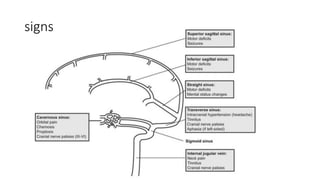

The document discusses lateral sinus thrombosis, also known as lateral sinus thrombosis or Otogenic suppurative thrombophlebitis, which is defined as the simultaneous presence of venous thrombosis and suppuration in the intracranial cavity. It is most commonly caused by b-hemolytic streptococcus and symptoms include nausea, vomiting, toxic and restless behavior, deep boring ear pain, and foul smelling blood tinged ear discharge. Management involves imaging, lumbar puncture of CSF to analyze volume, rate of formation, and composition.